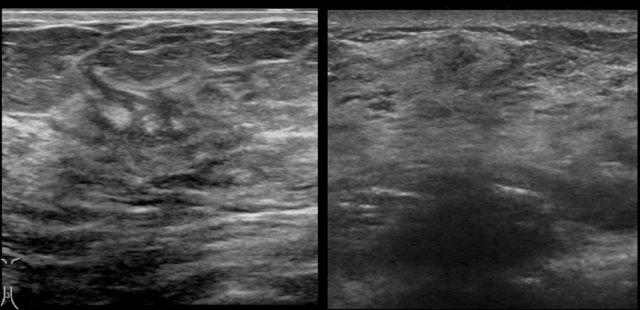

Các hình ảnh được chụp từ máy siêu âm Philips (trái) và Siemens (phải).

Hãy chú ý sự khác biệt trong cách hiển thị lớp da chẳng hạn.